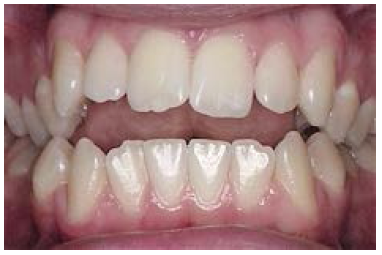

Figure 4. Deep bite.

Figure 4

Discrepancies: In a deep bite (overbite) (Figure 4), the maxillary incisors vertically overlap the mandibular incisors excessively. (In severe cases, mandibular incisors may contact the palate or maxillary incisor may strike mandibular gingiva.) In an open bite, there are areas where the maxillary and mandibular teeth do not touch. A patient can have an anterior or posterior open bite (Figure 5 and Figure 6). (An anterior open bite can sometimes be attributed to thumb sucking or a tongue thrust. Other times the condition is a skeletal problem.) Overjet refers to the distance between the facial surfaces of the maxillary incisors and the facial surfaces of the mandibular incisors.